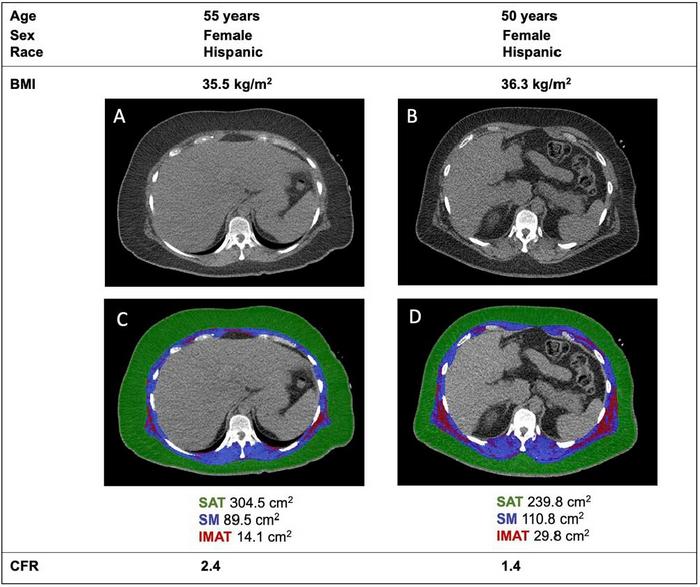

All the patients were tested with cardiac positron emission tomography/computed tomography (PET/CT) scanning to assess how well their hearts were functioning. Researchers also used CT scans to analyse each patient’s body composition, measuring the amounts and location of fat and muscle in a section of their torso.

To quantify the amount of fat stored within muscles, researchers calculated the ratio of intermuscular fat to total muscle plus fat, a measurement they called the fatty muscle fraction.